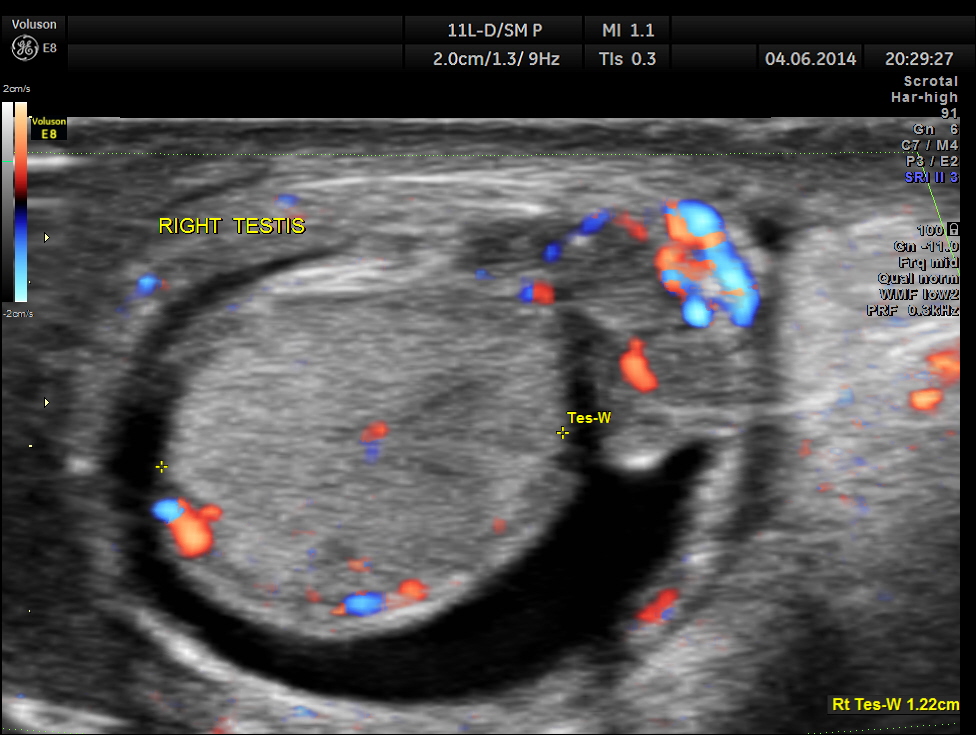

This was a 9-year-old boy , who was referred for evaluation of acute right scrotal pain of 2 days onset. He had mild right scrotal swelling and severe pain . One of the best uses of colour Doppler is for evaluation of acute scrotal pain , when the surgeon wants to rule out acute torsion . The other common condition is acute inflammation , which is medically managed. The images with colour just tell the story .

Rt Testis has normal appearance , with enlargement of the right epididymis . Colour flow imaging shows normal flow in the scrotum and increased flow in the epididymis , suggestive of acute inflammation – Acute Epididymitis.

Mild hydrocele is also seen.